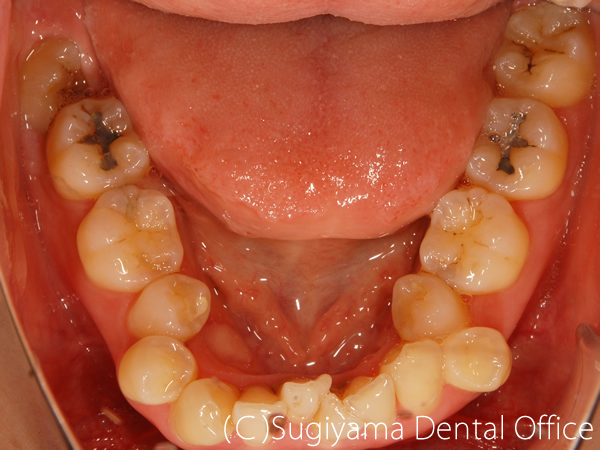

術前症例写真

術後症例写真

前歯を綺麗にしてほしいということで来院した女性の患者さんです。

親知らずは抜歯しましたが、そのほかは1本も歯を抜かずに矯正治療を仕上げました。

変色が著しかった前歯2本はオールセラミッククラウンで治しました。

歯が綺麗になったことで、笑顔がさらに美しくなりました。